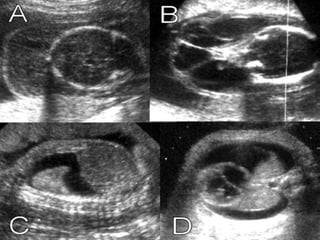

CARACTERÍSTICAS

ECOGRÁFICAS

ASCITIS

•DESDE PEQUEÑAS COLECCIONES.

•ACUMULACIONES MAYORES.

DERRAME PLEURALY O

PERICARDICO.

•UNILATERALES.

• BILATERALES.

•PEQUEÑOS.

•GRANDES.

DERRAME PLEURAL

EDEMA SUBCUTÁNEO

•GENERALIZADO.

•LOCALIZADO.

•LIMITADO A LA PARTE SUPERIOR O

INFERIOR DEL CUERPO.

EDEMA DE LA

PLACENTA

•GROSOR MAYOR A 6 CM PARA EL TERCER

TRIMESTRE

DIAGNÓSTICO

ECOGRÁFICO

PRESENCIA DE DOS O MÁS DE LOS

SIGUIENTES HALLAZGOS:

•ASCITIS FETAL

•DERRAME PLEURAL

•DERRAME PERICÁRDICO

•EDEMA SUBCUTÁNEO (MAYOR A 5 MM)

•HIGROMA QUÍSTICO

•POLIHIDRAMNIOS (50-75%)

•ENGROSAMIENTO DE LA PLACENTA

(MAYOR A 6 CM)